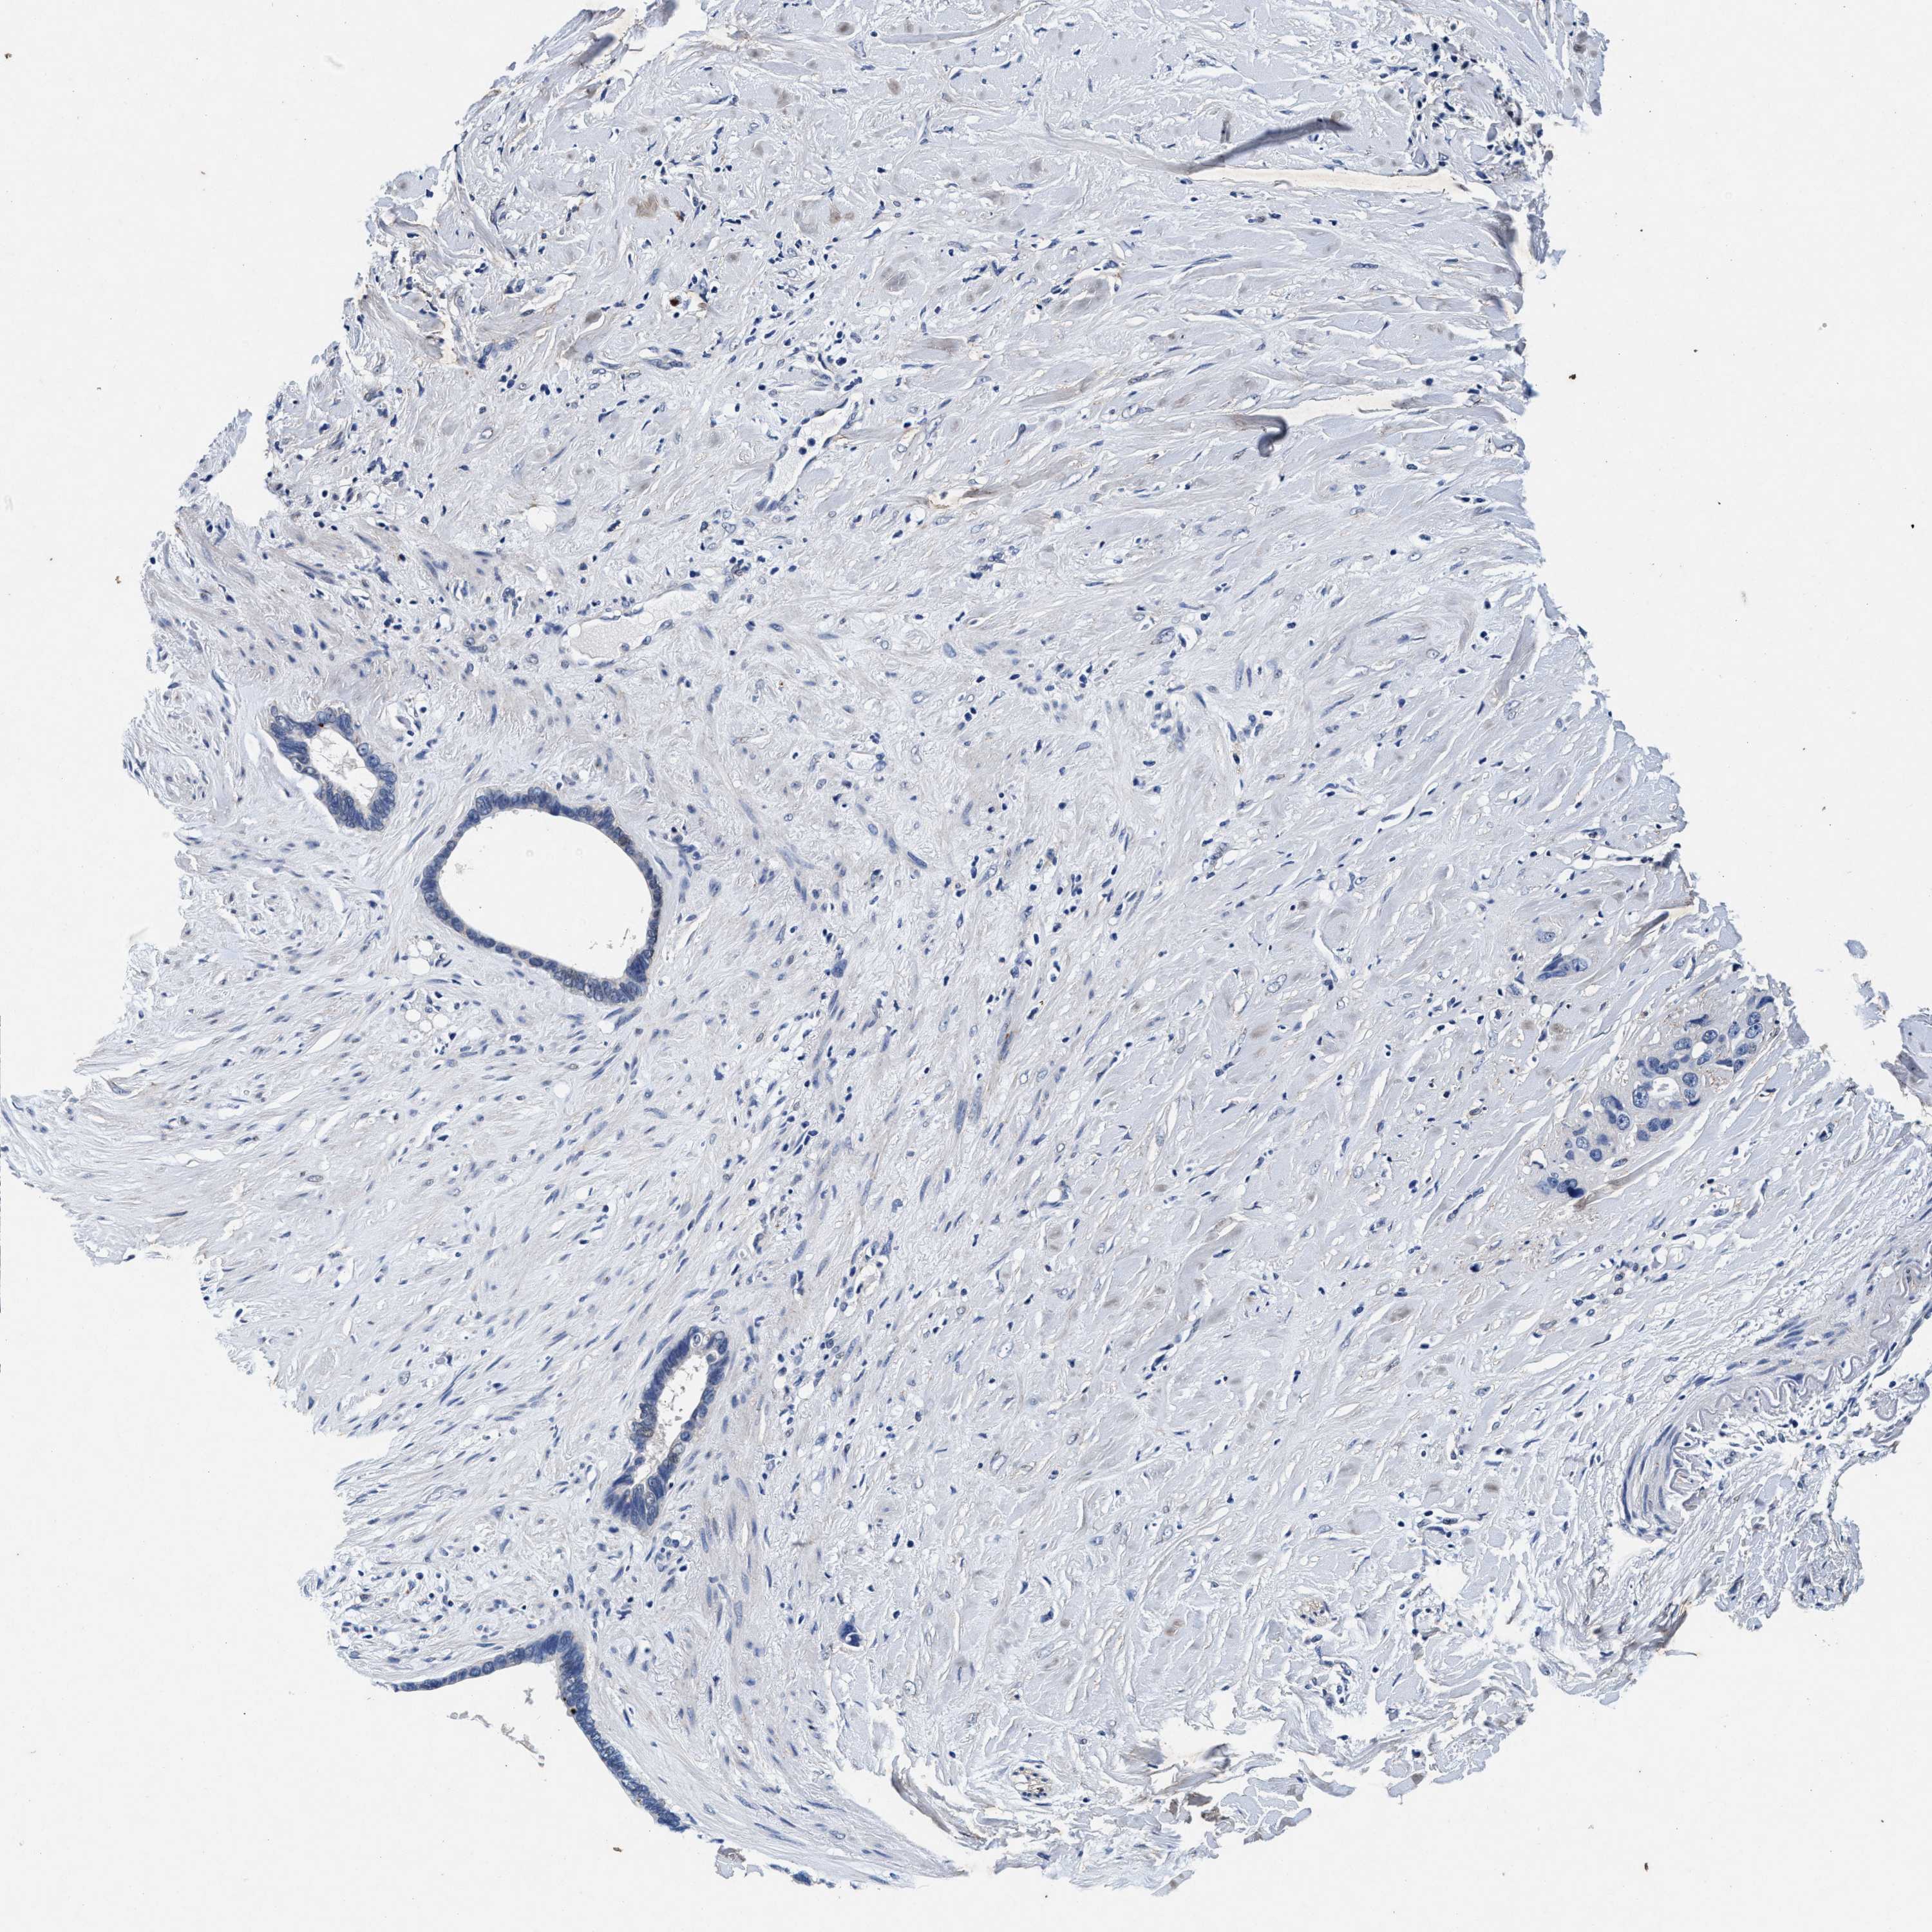

LIVER CANCER - Protein expressioni

A mouse-over function shows sample information and annotation data. Click on an image to view it in a full screen mode. Samples can be filtered based on level of antibody staining by selecting one or several of the following categories: high, medium, low and not detected. The assay and annotation is described here.

Note that samples used for immunohistochemistry by the Human Protein Atlas do not correspond to samples in the TCGA dataset.

Antibody stainingi

Antibody staining in the annotated cell types in the current human tissue is reported as not detected, low, medium, or high, based on conventional immunohistochemistry profiling in selected tissues. This score is based on the combination of the staining intensity and fraction of stained cells.

Each image is clickable and will lead to virtual microscopy that enables deeper exploration of all samples and also displays staining intensity scores, fraction scores and subcellular localization as well as patient and tissue information for each sample.

Antibody CAB022694

Staining

High

Medium

Low

Not detected

Intensity

Strong

Moderate

Weak

Negative

Quantity

>75%

75%-25%

<25%

None

Location

Nuclear

Cytoplasmic/membranous

Cytoplasmic/membranous,nuclear

Cholangiocarcinoma

Carcinoma, Hepatocellular, NOS